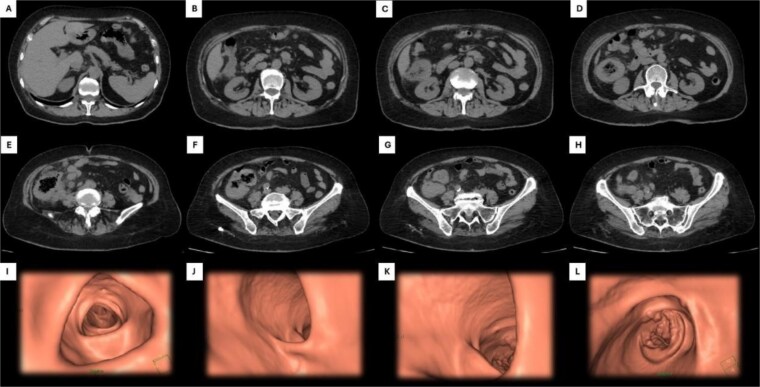

Primary colonic lymphoma: clinical dilemmas in diagnosis and treatment strategy.